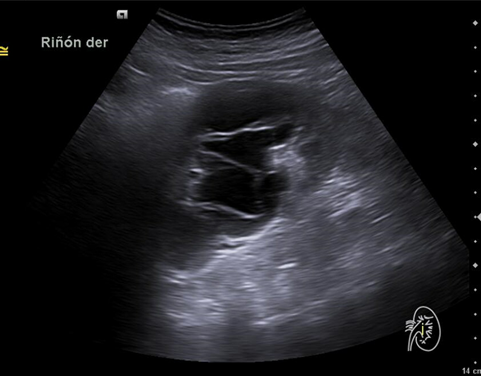

Hallazgos ecográficos

Riñón derecho 9,9 cm con morfología y ecogenicidad conservada. Presenta hidronefrosis grado III. No se identifica causa obstructiva.

Estenosis de unión pieloureteral. Diagnóstico diferencial: cólico renoureteral (CRU), ITU Pielonefritis aguda. Tras realizar pruebas complementarias así como valoración por Urología se diagnosticó como Estenosis de unión pieloureteral derecha.

Se remite a la paciente a Urgencias donde fue dada de alta con diagnóstico de CRU y tratamiento con Fosfomicina. Consultó al día siguiente, persistiendo el dolor y febrícula, remitiéndose de nuevo a Urgencias. Solicitan estudio de imagen con ecografía y ante los hallazgos se amplió el estudio a TC simple de abdomen: Hidronefrosis grado III con líquido perirrenal sugestivo de rotura de fórnix. Nefrolitiasis puntiformes en ambos cálices inferiores. Sin clara causa obstructiva objetivable. Se contactó con Urología de guardia quien propuso tratamiento ambulatorio con seguimiento posterior y colocación de nefrostomía programas y pielografía para estudio de probable estenosis de unión pieloureteral. Actualmente la paciente permanece en seguimiento por urología.